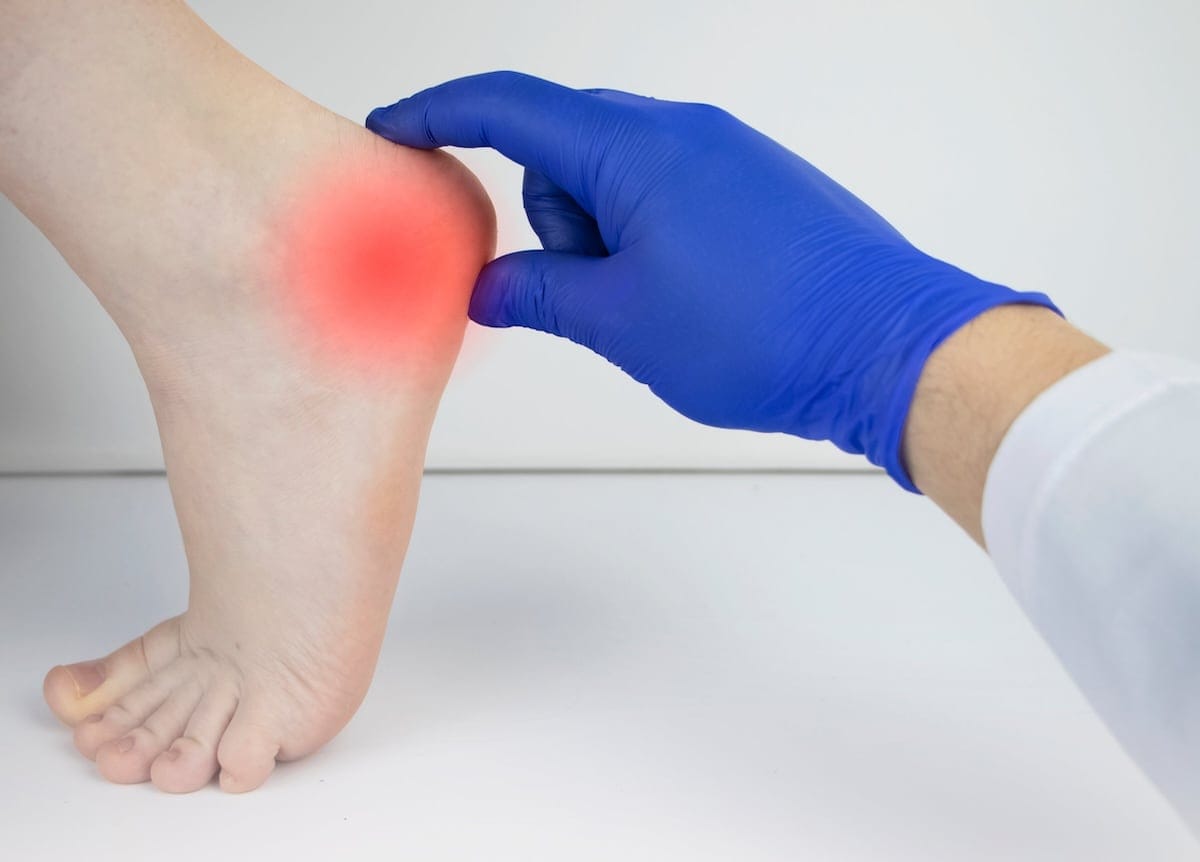

A dor na parte de trás do calcanhar, que piora com o movimento e pode apresentar inchaço, é um forte indicativo. Se a dor persistir, procure um médico para ter o diagnóstico correto.

A tendinite de Aquiles é aquela dor chata que aparece na parte de trás do seu calcanhar, bem ali onde o músculo da panturrilha se liga ao osso do pé. Sabe, é uma inflamação desse tendão forte que usamos para correr, pular e até para andar. Quando exigimos demais dele, ou quando ele já está cansado e fraco, o problema aparece.